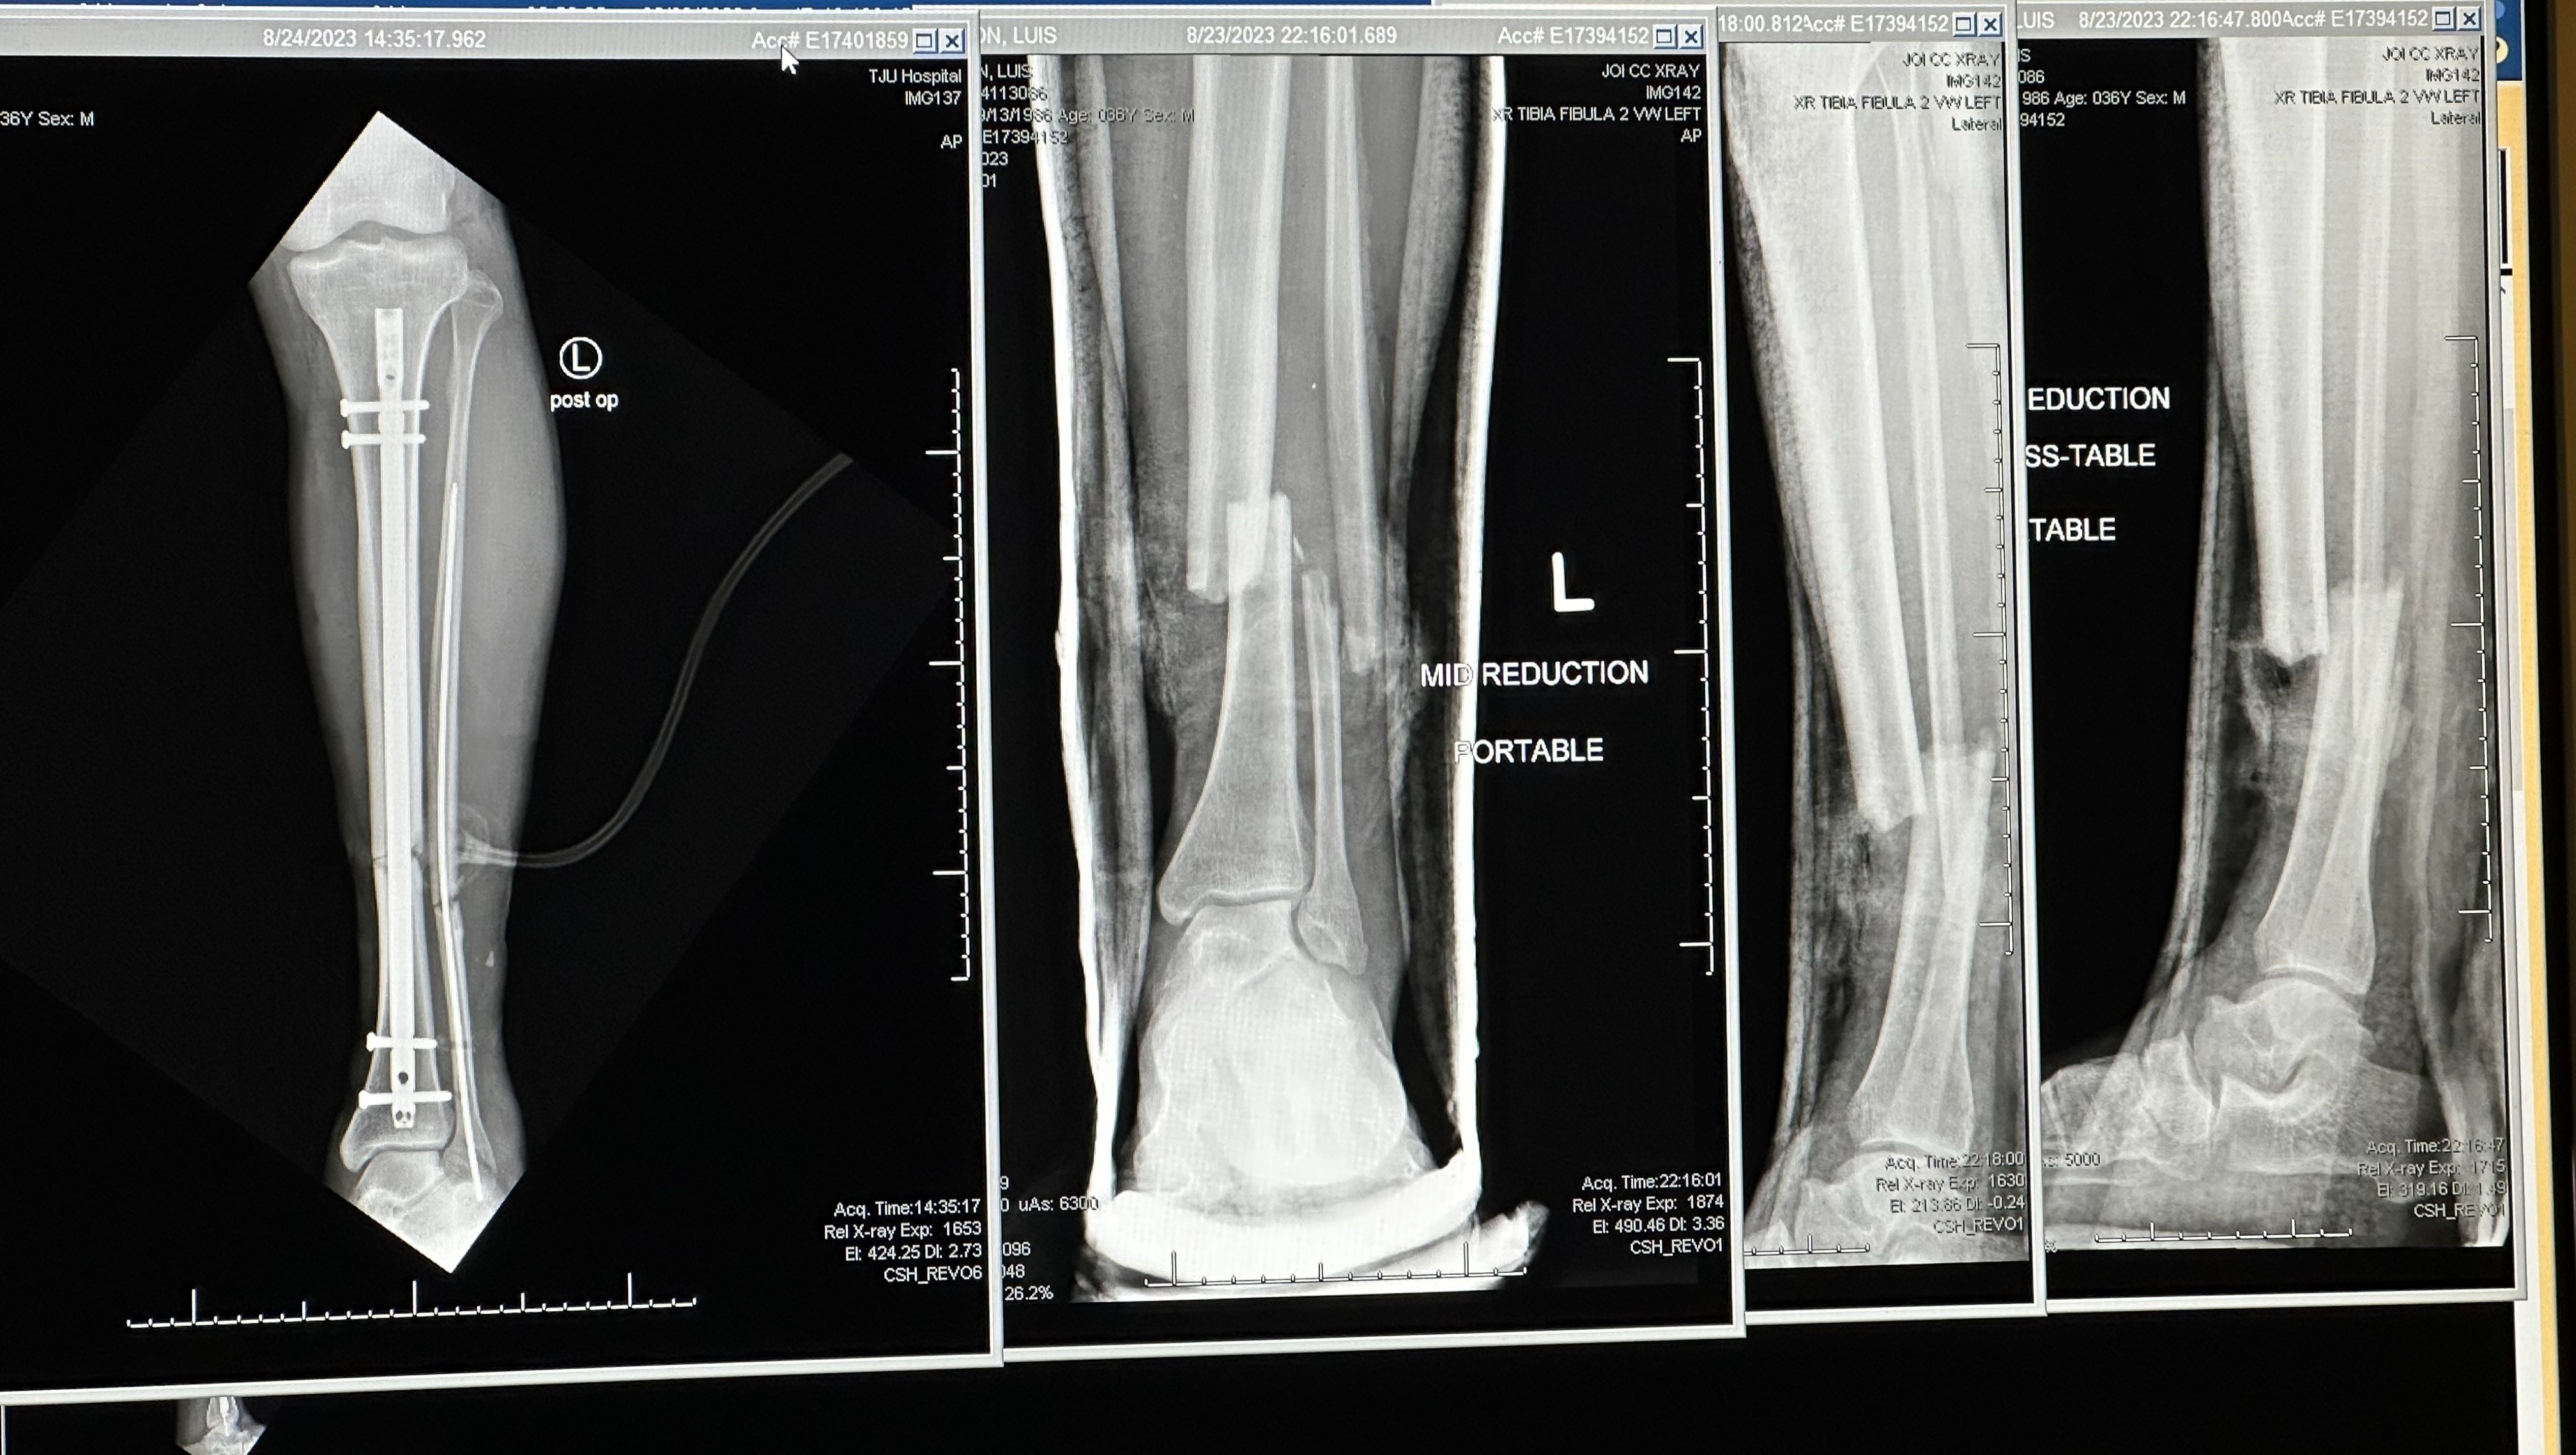

On August 23rd, Luis was severely injured in a hit-and-run. He was struck by a car on 676 that did not stop after they hit him. The accident inflicted serious injuries and wounds to his lower legs. He broke his tibia and ankle, injured his knee, endured major wounds and more. We're thankful for the passersby who stopped on the highway, the state troopers who wrapped his legs, the EMTs and the incredible staff at Jefferson Hospital in Philly for saving his life, and his legs.